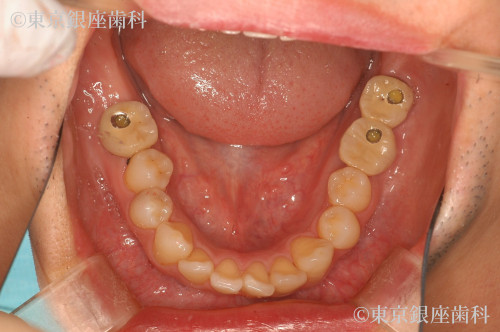

ひどい虫歯で歯がボロボロ

Before

施術内容 インプラント

インプラント及びセラミック処置を実施